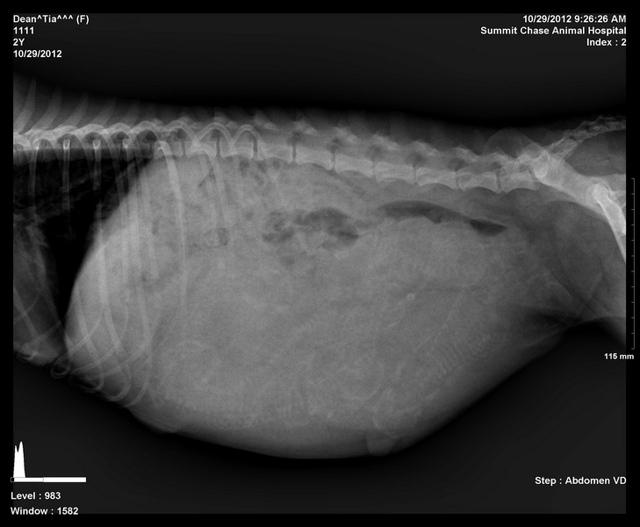

Ti preg xrays 2 10 30 12

How many skulls and spines can you see, click on pic to enlarge.